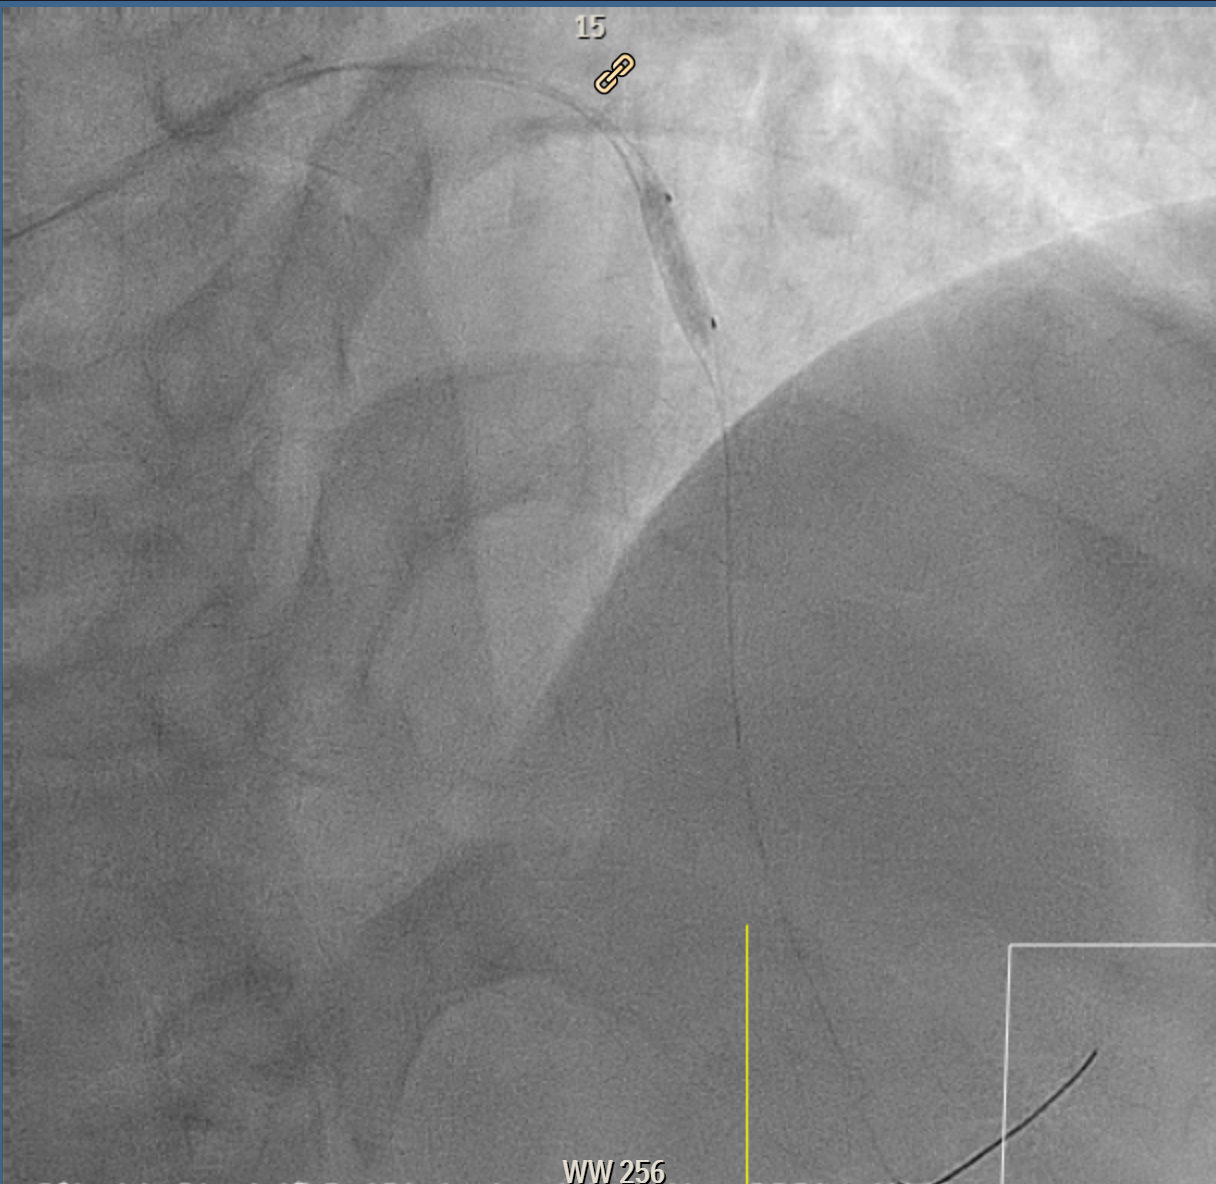

Coronary intervention was performed on a proximal LAD (pLAD) total occlusion via single right radial approach using 6F XB 3.5 guiding catheter. Initial antegrade attempts with RunThrough Floppy and Fielder-XT wires were unsuccessful due to buckling against the proximal cap. Wire strategy was escalated to Gaia Second wire with Finecross microcatheter support, allowing careful penetration of proximal cap and subsequent advancement through distal cap. True lumen position was confirmed with contrast injection through the microcatheter, and wire was then exchanged to a Fielder-XT wire to safely navigate to distal LAD (dLAD) and reduce risk of perforation. Lesion preparation was performed with stepwise predilatation, beginning with Sapphire 0.85 ¡¿ 5 mm balloon at 10–12 atm in pLAD to dLAD. Further predilatation was performed with Sapphire 2.0 ¡¿ 15 mm balloon at 12 atm from dLAD to mid LAD (mLAD) and higher pressure up to 16atm at pLAD. Despite multiple inflations, pLAD remained tight, prompting escalation with a Sapphire 2.5 ¡¿ 15 mm balloon at up to 18 atm and Scoreflex NC 3.0 ¡¿ 15 mm balloon at 8–12 atm to adequately prepare mildly calcified pLAD segment. Final predilatation achieved optimal luminal caliber. DCB was then performed, with m-dLAD treated using Magic Touch 2.25 ¡¿ 35 mm and the p-mLAD treated with Magic Touch 3.0 ¡¿ 40 mm. Both were deployed at 8 atm for 60 seconds. The procedure resulted in excellent luminal gain with no residual stenosis, recoil, or perforation.